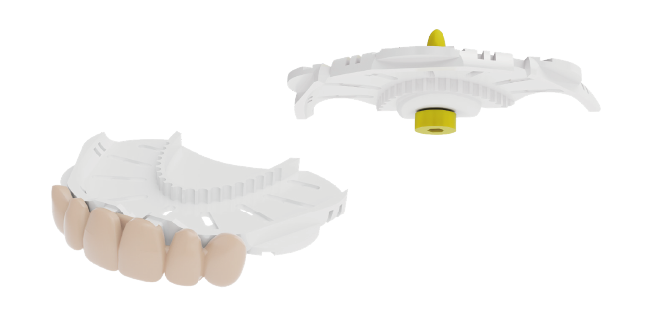

Digital denture production

Digital denture designed from existing dental CAD software (3Shape, exocad, etc.)

Digital denture production

Digital denture designed from existing dental CAD software (3Shape, exocad, etc.)